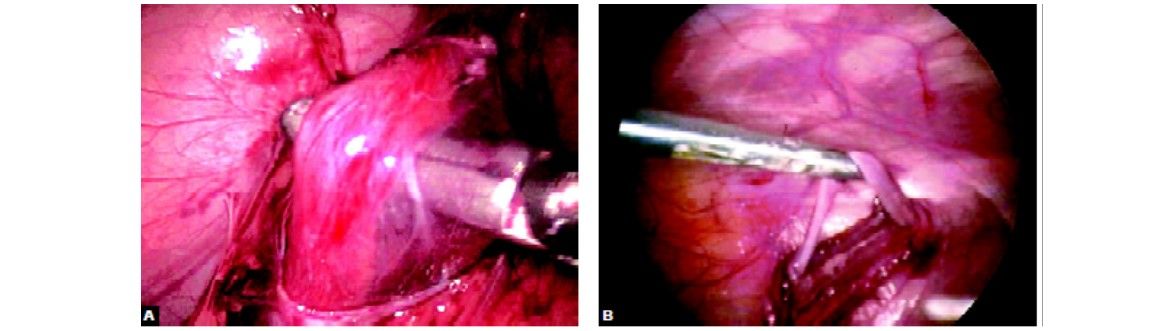

The intra-abdominal vas deferens can be identified as structure joining the spermatic cord above the internal inguinal ring. The gonadal vessels are visualized easily in the retroperitoneum. The posterior peritoneum is excised with cautery, laser, or endoscopic scissors. The gonadal vessels are then mobilized; however, reliably identifying the spermatic artery and its branches are sometimes difficult through the laparoscope. Therefore, many surgeons prefer to use the laparoscopic Doppler probe to facilitate the identification of the spermatic artery during laparoscopic varicocele ligation. The Doppler probe is 28.58 cm long and fits through a 5 mm laparoscopic port. After identifying the gonadal artery, the surgeon isolates the gonadal vein or veins using blunt dissection with atraumatic graspers.

Laparoscopic varicocelectomy

The spermatic vein is identified

Endoscopic clip applier is used to secure it or intracorporeal suturing is used to ligate the gonadal vein or veins while sparing the artery.